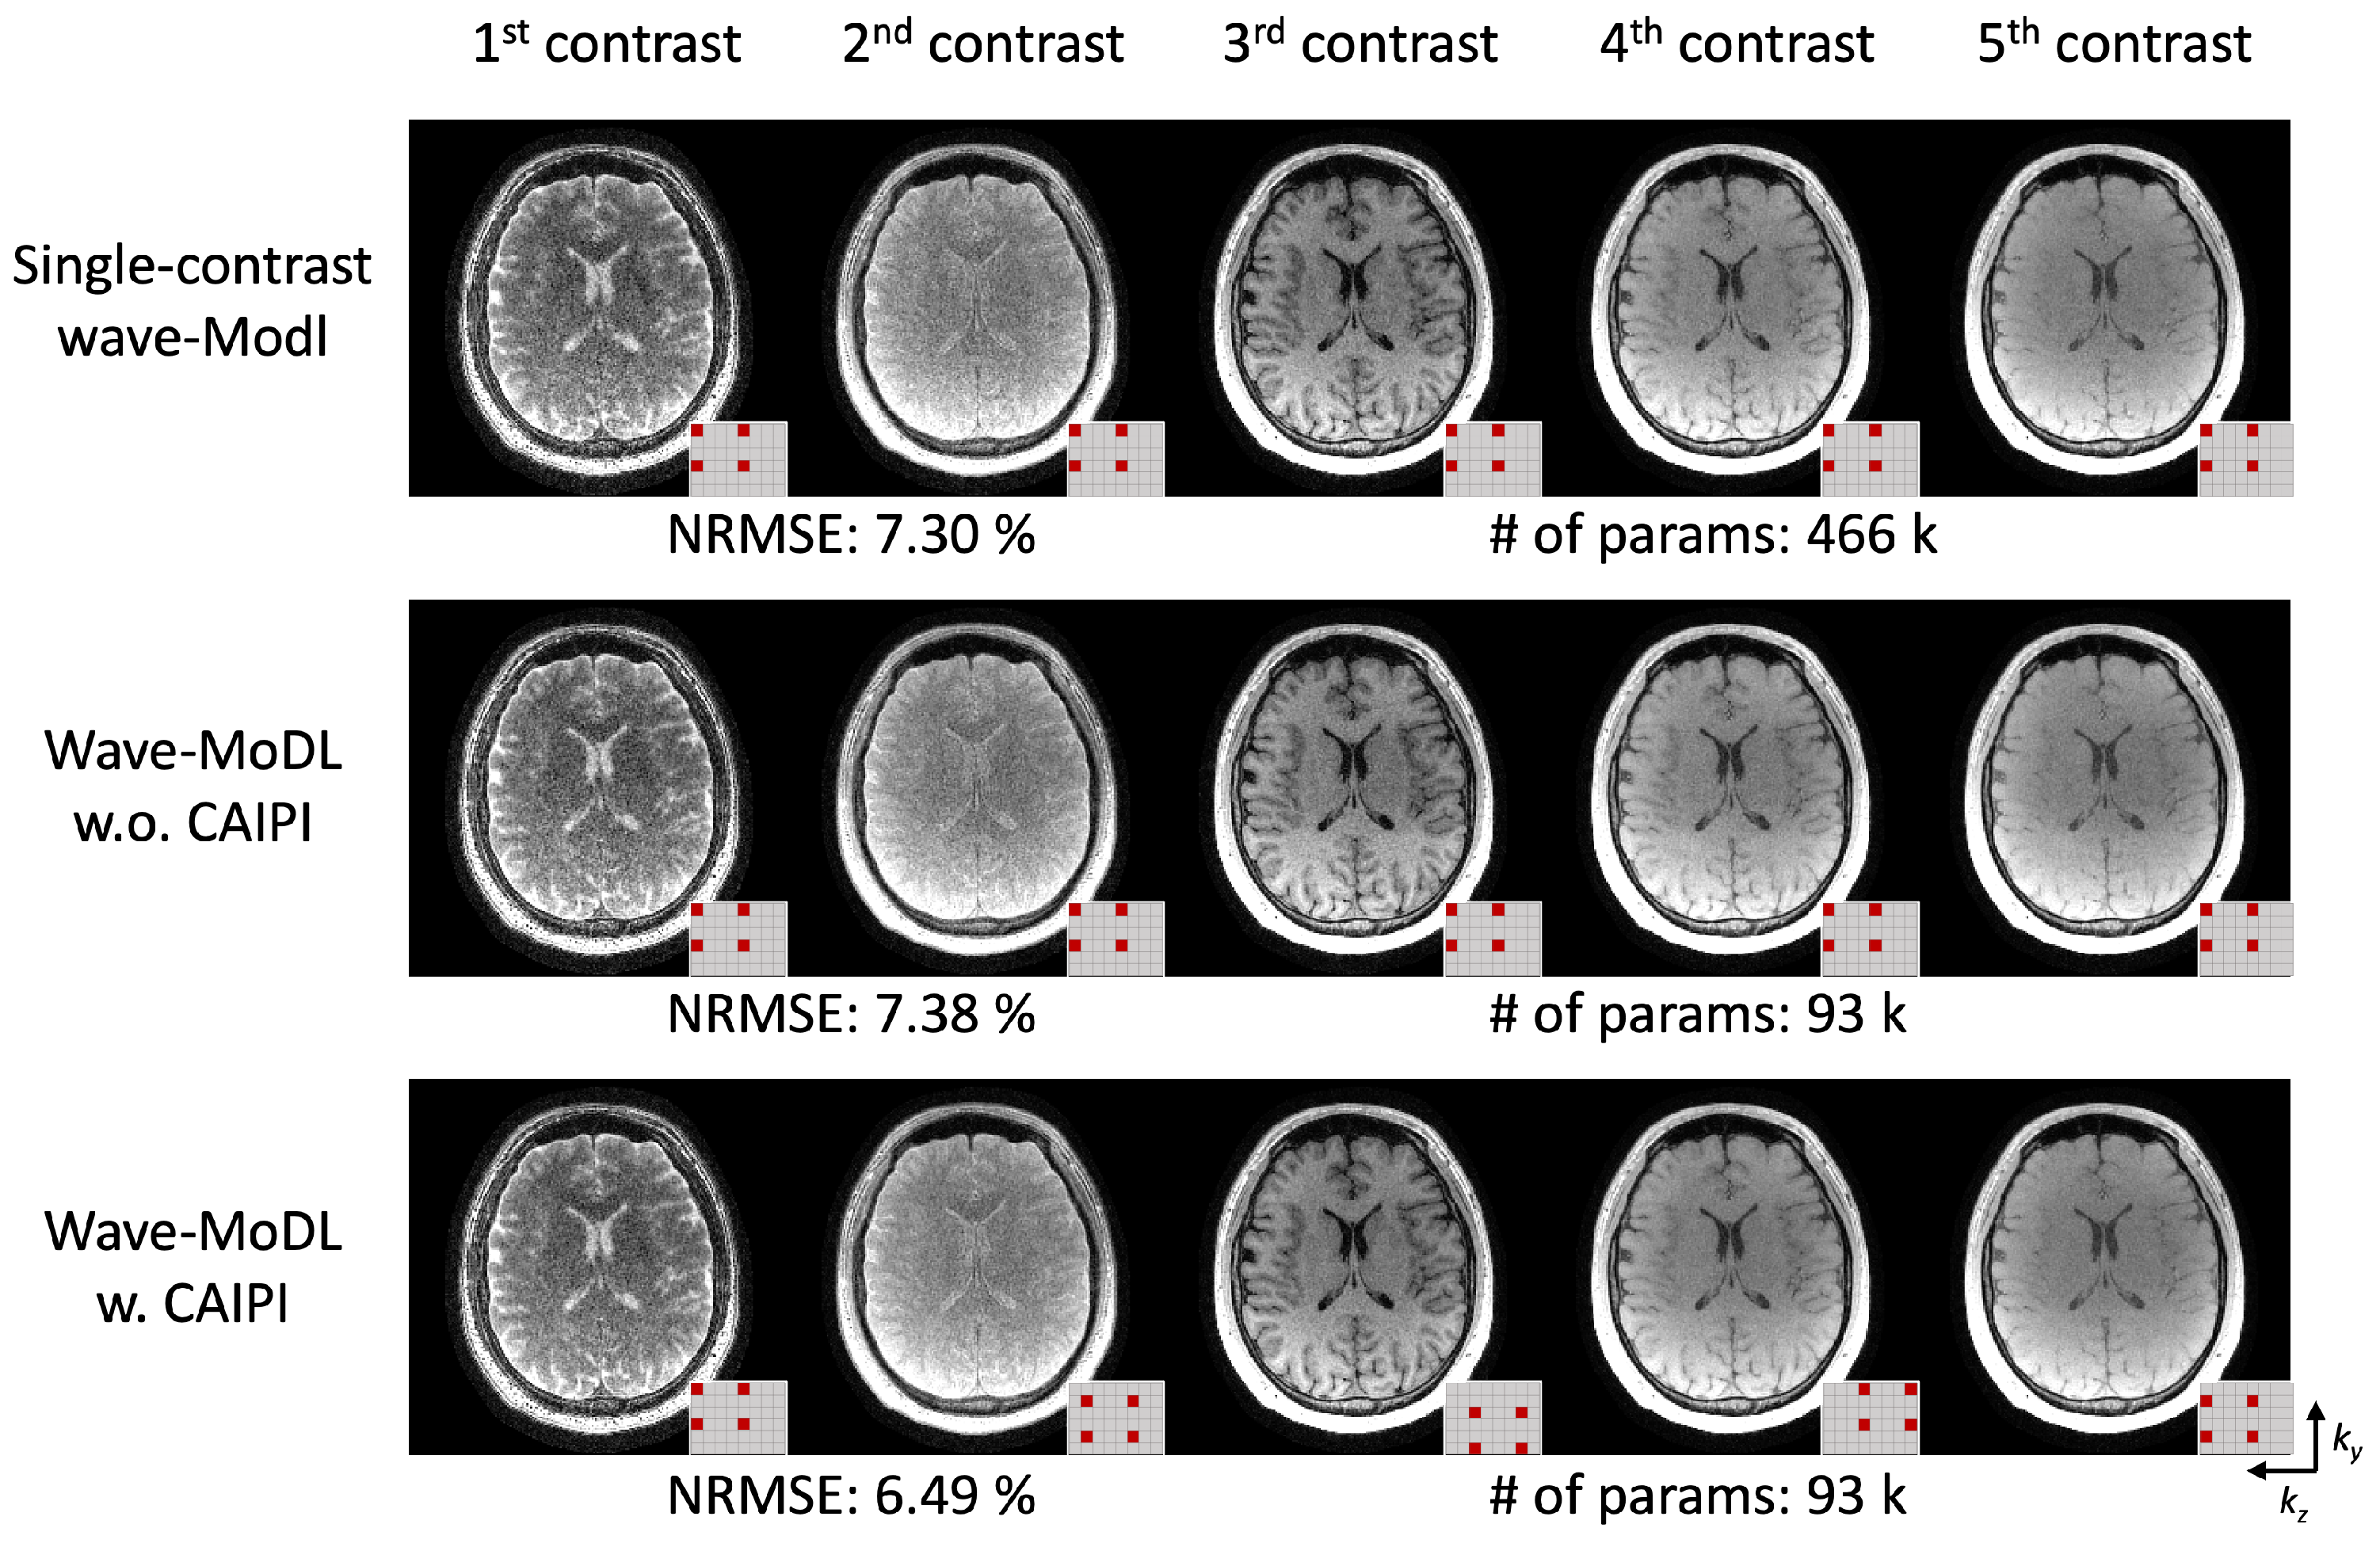

4.3. 3D-QALAS at R = 4 × 3